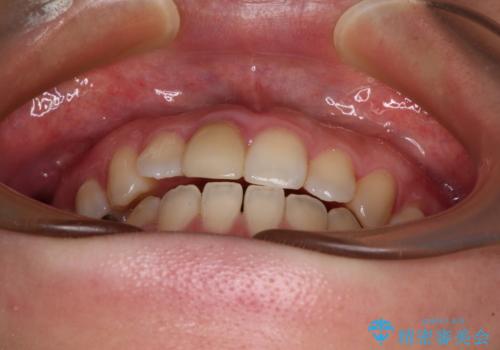

【モニター】後戻りでできた隙間 ワイヤー装置での再矯正

- 学生時代に行った抜歯矯正の後戻りで、隙間ができてしまったことを気にして来院された患者様です。

マウスピース矯正を検討されていましたが、後戻りの隙間が非常に大きく、奥歯を前方に移動させる必要があるため、ワイヤー装置にて矯正治療を行うこととしました。

舌の突出癖が非常に強く、その影響で隙間ができてしまったので、舌のトレーニングをしっかりと行っていただきました。